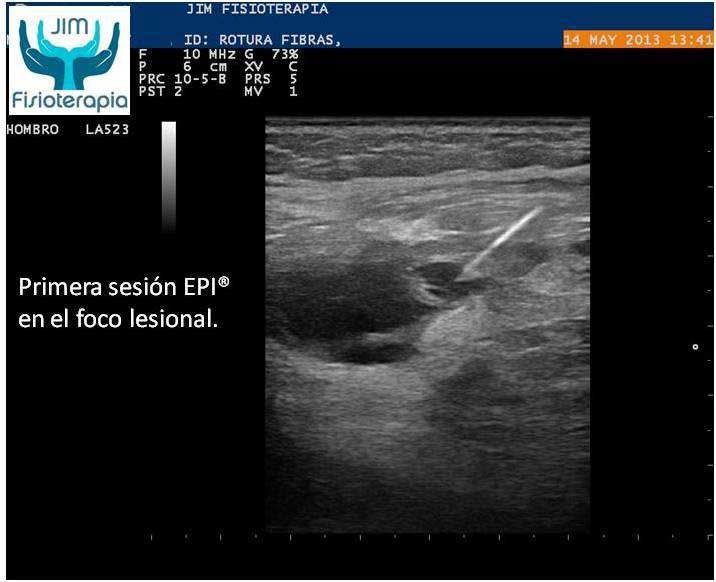

Varón de 47 años, sufre una rotura muscular en el bíceps femoral de la pierna derecha al realizar una brusca contracción excéntrica asociada a movimiento de torsión, al evitar la caída de su motocicleta. Acude a las 72 hrs a nuestra clínica presentando dolor a la palpación, contracción muscular y en la marcha. En la exploración ecográfica se observa una rotura de bordes irregulares.

Se procede a la aplicación de EPI® con el fin de “vaporizar” el derrame producido y favorecer el proceso de regeneración y cicatrización muscular sin fibrosis. En las imágenes se puede apreciar el cambio en el tejido desde la primera sesión, fueron necesarias cuatro sesiones de EPI® hasta lograr la recuperación completa, a partir de la segunda sesión el paciente refirió una desaparición del dolor en la marcha y las actividades cotidianas, complementando su tratamiento con la aplicación de Radiofrecuencia.